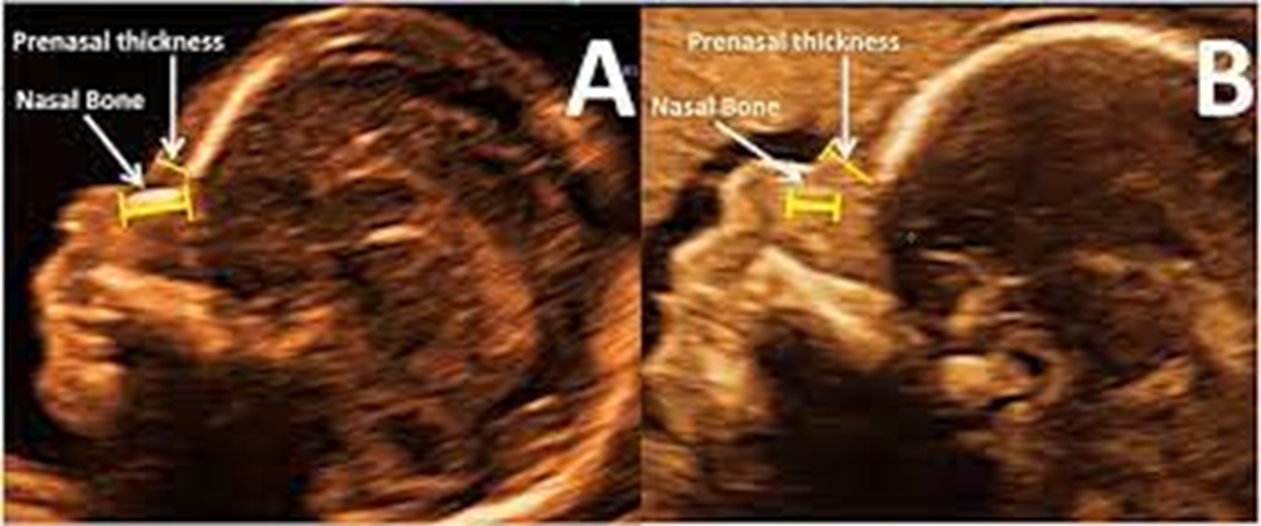

when measuring nuchal fold what do you have to have in image

CSP

nuchal fold where to measure

outer skull to outer skin

thickened nuchal fold

nuchal fold measurement routinely performed ___ - ___ weeks

15-19.6

nuchal fold measurement should be less than ___ mm

6 mm

nuchal fold calipers